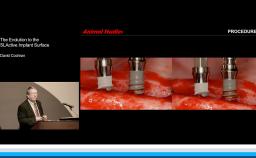

This lecture presents histomorphometric studies to demonstrate the strong relationship between bone and implant design, especially at the implant-abutment interface. The presenter shares key factors to explain the response of hard and soft tissue at the very first step of osseointegration. He focuses on the interaction between the design of the implant and the bone physiology. He develops the relationship between bone resorption and the inflammatory response of the host. The presenter also discusses different ways to decrease the inflammatory response at the implant-abutment interface. Supported by literature, a complete review of the various implant designs and their interactions with the bone is presented. The three major implant types are discussed: one-piece implant; two-piece implant with butt-joint interface; and two-piece implant with platform switching connection. This is a cutting edge lecture on the bone-implant relationship.